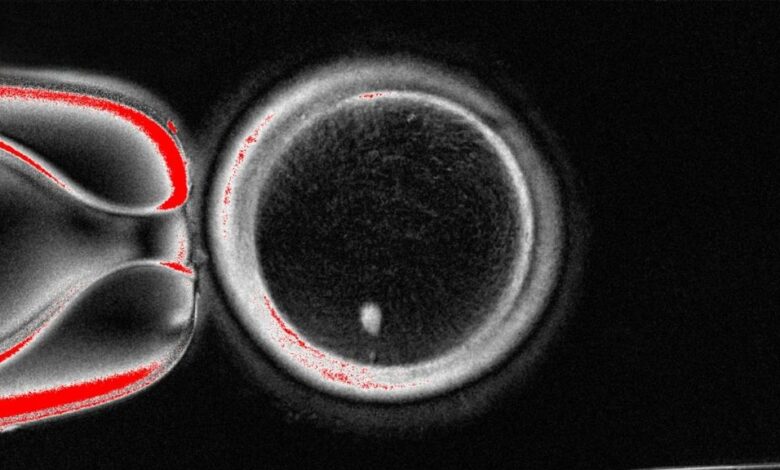

El óvulo reconstruido, que originalmente contenía 46 cromosomas como cualquier célula del cuerpo, logró reducir su número a 23 de forma artificial. La división cromosomática es un proceso clave para la fecundación . Con la carga genética adecuada, el óvulo quedó listo para recibir el resto de material genético que aporta el espermatozoide y completar la fecundación.

En total, el equipo creó 82 ovocitos funcionales y los fertilizó con esperma de un donante sano mediante fecundación in vitro. Aunque los ovocitos iniciaron el proceso de división celular, ninguno progresó de forma significativa. Solo el 9 % alcanzó la etapa de blastocisto, considerada la “primera semilla” que se adhiere al útero. Los investigadores afirmaron que seguirán trabajando para mejorar el desarrollo de los óvulos fecundados.